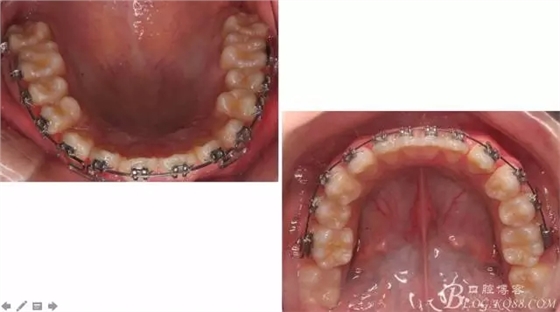

佩戴三個(gè)月的FR2, 效果奇佳!前牙基本達(dá)到淺覆蓋,淺覆合!接下來進(jìn)入二期直絲弓固定正畸,排齊階段!

接下來盡管配合些雙側(cè)后牙對(duì)角牽引,咬合關(guān)系依,不盡人意。

下頜配合多曲方絲,三角牽引,調(diào)整咬合。